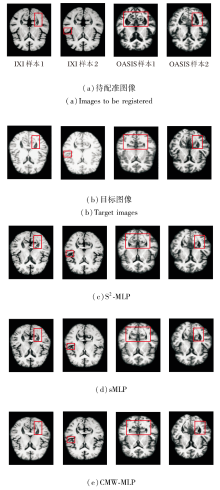

CMW-MLP作为PyraMLP-Net的核心组件, 通过计算输入特征间的局部相关性以捕获多范围依赖关系.为了验证其必要性, 以PyraMLP-Net为基准, 将CMW-MLP分别替换为S2-MLP(Spatial-Shift MLP)[25]和sMLP(Sparse MLP)[26]进行对比.

同样在IXI、OASIS数据集上各选取2个样本, 各模块的图像配准结果如图13所示, 对PyraMLP-Net性能的影响如图14所示.由图可看出, CMW-MLP在IXI、OASIS数据集上的配准精度均显著高于S2-MLP和sMLP.这一优势主要源于其两项核心设计.

1)三维相关层显式建立局部特征的空间对应关系, 提供像素级对齐的强引导信号.

2)多窗口并行架构能同时捕捉不同尺度的空间依赖.相比之下, S2-MLP和sMLP仅能进行全局、无差别的特征混合, 缺乏对局部结构关联的显式建模和对多尺度形变的针对性处理, 因此难以精准捕捉解剖细节的对应关系.